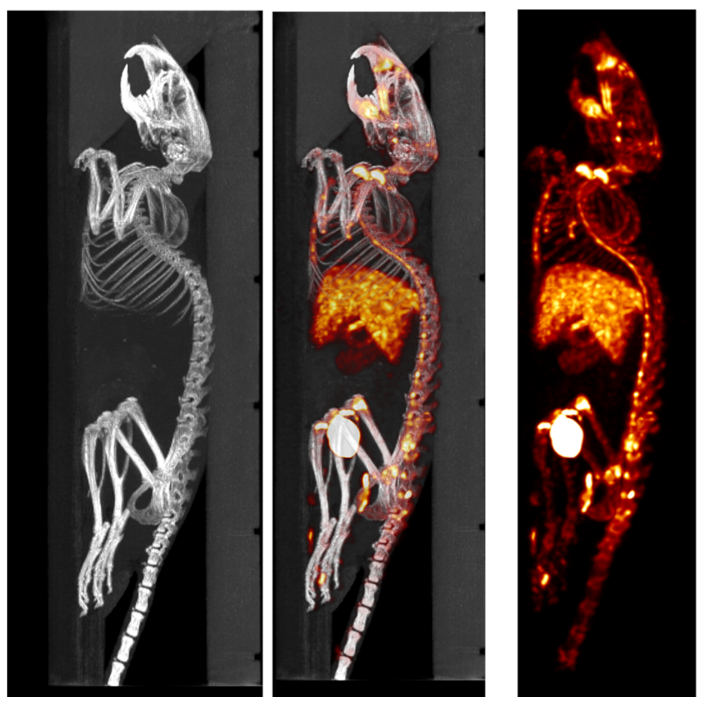

SPECT/CT組合圖像,小鼠的骨骼成像:99mTc-HDP,94.35MBq (2.55mCi) @ start acquisition,采集時間60min。

骨骼成像.png

SPECT/CT組合圖像,大鼠的骨骼成像:99mTc-HDP,200MBq,采集時間45min。